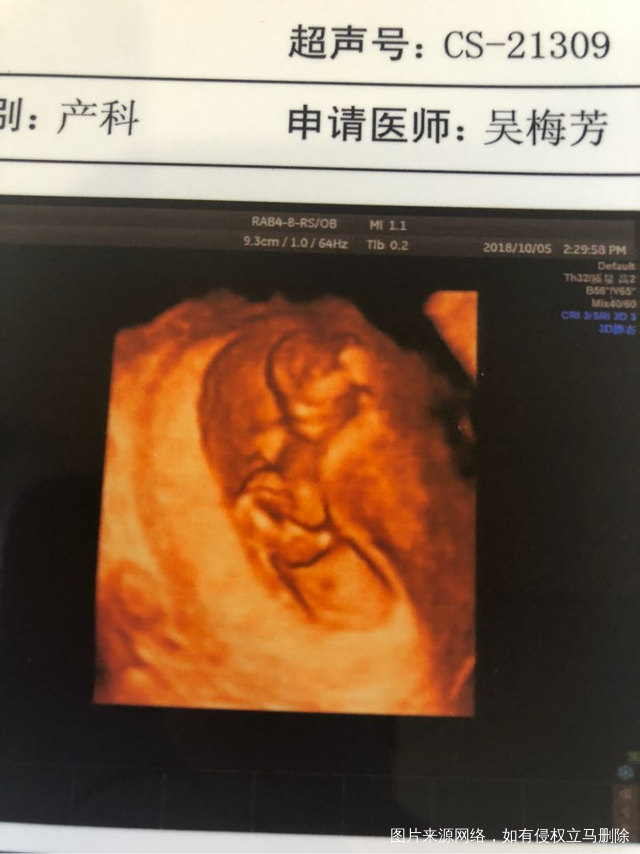

嘿嘿 抓怕到你坐着了